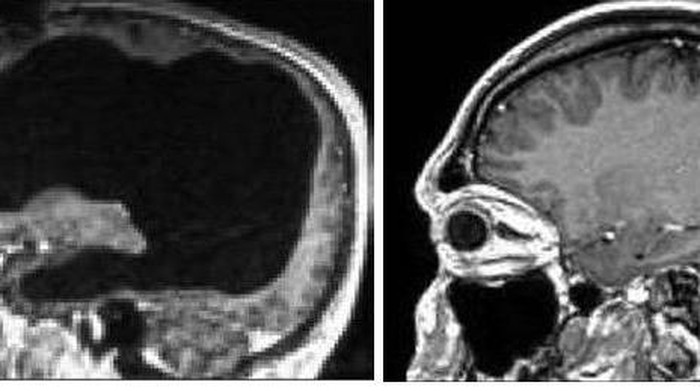

Suatu hari, pria ini mendatangi sebuah rumah sakit karena kakinya terasa layu. Tak disangka saat berupaya mencari tahu penyebab kaki pria ini lemas, dokter yang menanganinya justru menemukan bahwa sebagian besar bagian otak pria ini tidak berada pada tempatnya alias hilang.

Salah seorang ahli saraf yang ambil bagian dalam mengamati pasien ini memperkirakan pasien kehilangan lebih dari 50 persen atau bahkan 75 persen otaknya. Namun ia sama sekali tidak memperlihatkan 'efek samping' dari kondisi demikian.

Usut punya usut, saat masih berumur 6 bulan, pasien mengalami 'postnatal hydrocephalus', atau penumpukan cairan otak yang berlebihan dalam otak. Pada saat ia dilahirkan, dokter sempat memasukkan alat untuk mengeluarkan cairan dalam otaknya.

Tapi ketika alat itu diambil saat usia pasien menginjak 14 tahun, cairannya menumpuk lagi dan menekan otaknya. Setelah 30 tahun, cairan otak yang menekan tadi akhirnya menyisakan sebagian kecil otak saja, kira-kira seukuran kerang.

Dokter lantas memasukkan alat untuk mengeluarkan cairan dari otak pasien, dan dari situ kaki lemas pasien perlahan menghilang. Terlepas dari itu, pria ini dalam keadaan sehat, dan memiliki pekerjaan mapan sebagai pegawai negeri sipil, meskipun IQ-nya berada di bawah rata-rata.

Namun hingga akhirnya kasus ini dipublikasikan dalam jurnal The Lancet beberapa waktu lalu, para ahli saraf tak dapat menjelaskan bagaimana otak pria ini dapat berfungsi sebagaimana mestinya, padahal bagian otak vital mengalami tekanan selama bertahun-tahun.